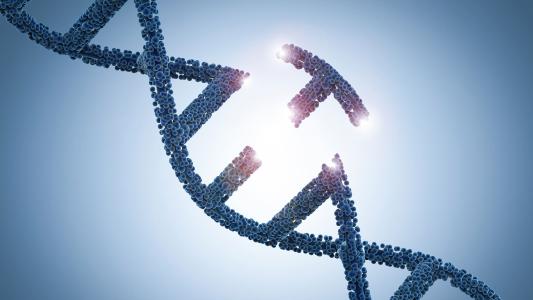

Small protein, big breakthrough for CRISPR gene editing

A new protein opens doors for gene editing by gaining access to hard-to-reach areas of the genome.

For the first time, researchers edit human mitochondrial DNA

Researchers can now edit a part of the human genome that CRISPR has never been able to. This opens up new possibilities for research and cures for devastating rare genetic diseases.

Gene writing: A new type of genetic engineering

Startup Tessera Therapeutics has developed gene writing, a new approach to genetic engineering that it says overcomes CRISPR’s shortcomings.